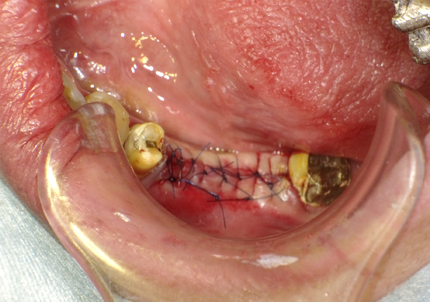

6.二次手術

インプラント周囲の角化歯肉(付着歯肉:骨に固定されてる歯肉)の獲得を目的に歯肉弁を移動する